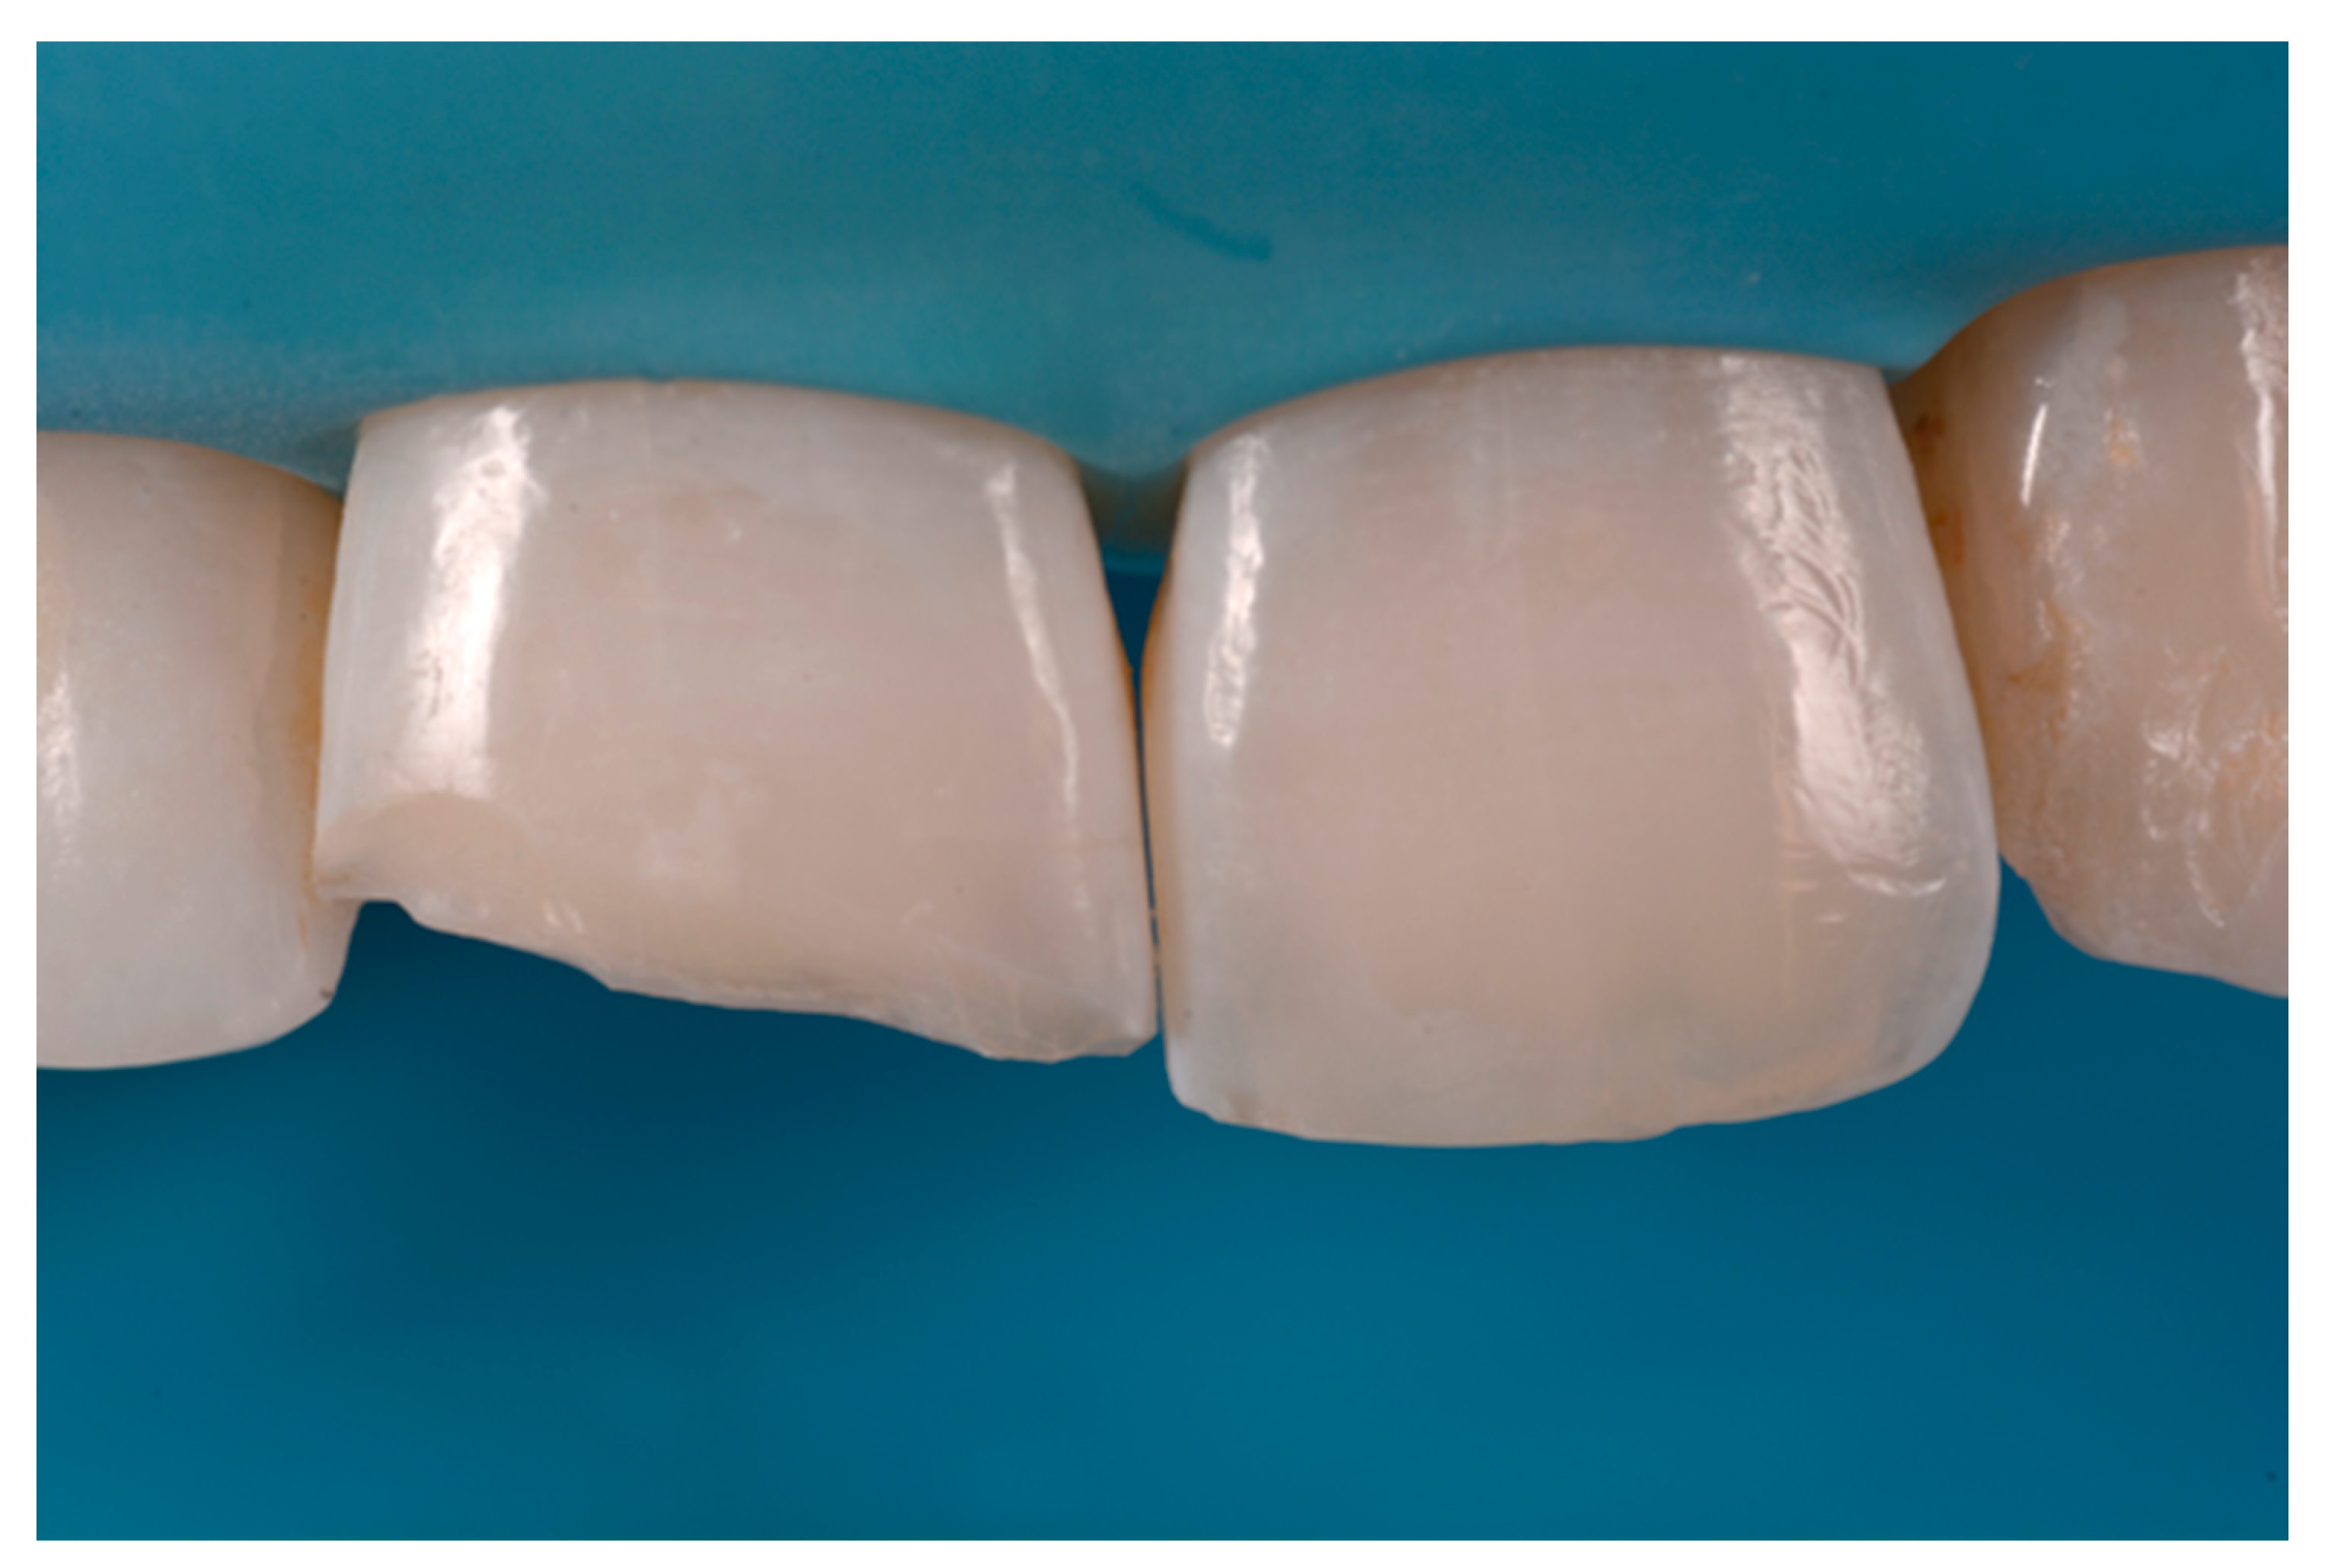

Once completed, the two frames (Clearfil Majesty ES-2, A1E, A2D, Kuraray Noritake Dental, Tokyo, Japan) showed internal and external excesses that were reduced using diamond burs and discs (Figure 33 and Figure 34) strictly following the procedure described in Section 2.1.2 of present article. Excesses were removed from the distal-incisal angle of #2.1 allowing therefore to obtain the desired translucency. After silane application and bonding procedure (Figure 35) as described in Section 2.1.2, restorations were completed (Figure 36 and Figure 37). They both show satisfactory clinical integration 1.5 years post-operative (Figure 38 and Figure 39).

Figure 33.

Frame imprecisions are corrected by reducing interproximal wall from the internal side. Reprinted from Restauri diretti nei settori anteriori, G. Paolone, S. Scolavino, © 2021, with permission from Quintessence Publishing Italy.

Figure 34.

Frame is also trimmed reducing external outline. Reprinted from Restauri diretti nei settori anteriori, G. Paolone, S. Scolavino, © 2021, with permission from Quintessence Publishing Italy.